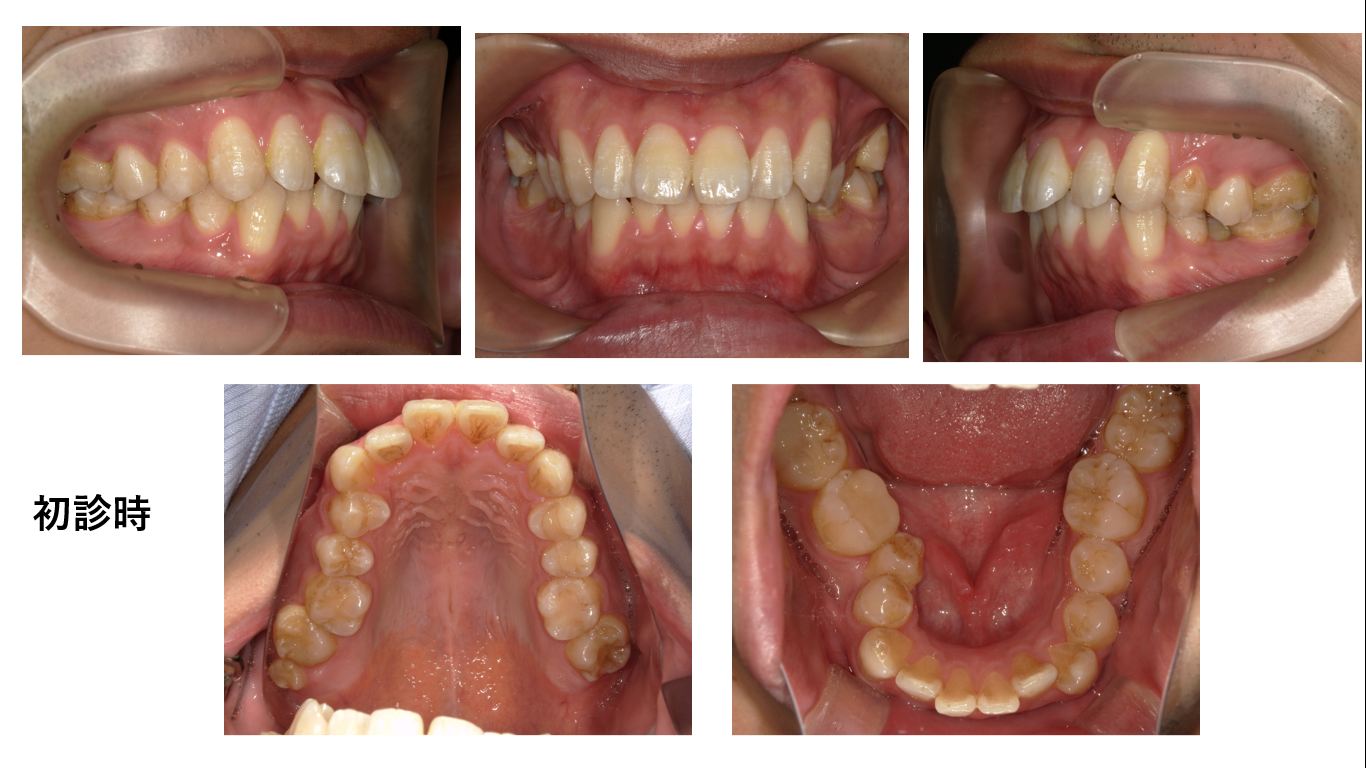

矯正症例141 AngleⅠ級 上下顎前突、ガミースマイル、口ごぼ

初診時15歳、治療期間3年、抜歯部位:上下顎4番、8番、治療費総額102万円(税込み)この症例も患者さんからHP掲載の許可を得ています。